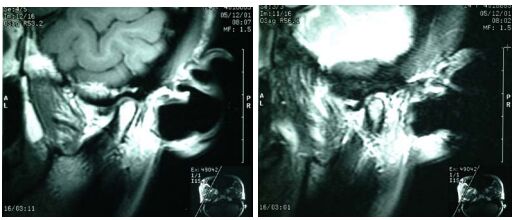

79.李小姐所接受的為何種斷層攝影?(A) 直線斷層攝影(linear tomography) (B) 螺旋斷層攝影(spiral tomography) (C) 電腦斷層攝影(computerized tomography) (D) 磁振攝影(MRI)